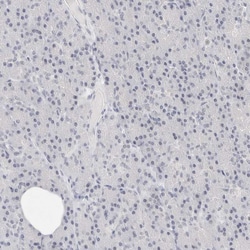

Invitrogen™ CD22 Polyclonal Antibody

CD22, also known as BL-CAM, is a type I transmembrane glycoprotein composed of two polypeptide chains, CD22alpha and CD22beta, with molecular weights of 130 and 140 kDa, respectively. These chains are produced by alternative splicing of the CD22 gene. CD22 is prominently expressed on mature B cells and B cell lymphomas, including hairy cell leukemia, diffuse large B-cell lymphoma, and nodular lymphocyte predominance Hodgkin's lymphoma, but is negative in classical Hodgkin's lymphoma. The extracellular portion of CD22 contains seven Ig-like domains that preferentially bind alpha2,6-linked sialic acid moieties found on epithelial, endothelial, B, and T cells. This binding can be masked by cis interactions with sialic acids on the same cell surface. CD22 expression is limited to late stages of B-cell differentiation, making it useful for phenotyping mature leukemias. Intracellularly, CD22 features six tyrosine residues within immunotyrosine-based inhibitory motifs (ITIM) and activation-like motifs. These residues are phosphorylated upon B-cell receptor engagement, allowing CD22 to regulate B-cell receptor signaling. CD22 participates in positive regulation through interactions with Src family tyrosine kinases and acts as an inhibitory receptor by recruiting cytoplasmic phosphatases via SH2 domains, which block signal transduction through dephosphorylation of signaling molecules. CD22's role in both positive and negative regulation of B-cell signaling, along with its specific expression pattern, makes it a valuable marker for antibody customers interested in B-cell-related research and diagnostics.

| Immunohistochemistry (Paraffin) | |